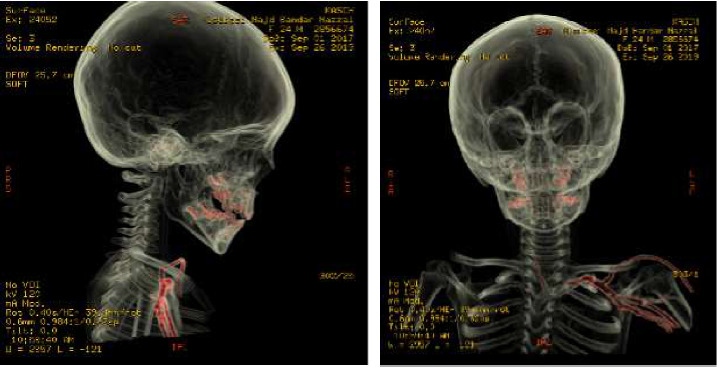

颈椎异物的病例被认为是罕见的,而针头移入椎管的病例是相当罕见的。记录最充分的案例是针灸针。我们报告一个2岁男孩的病例,偶然发现静脉注射针向后延伸至C7和T1棘间间隙,并在C5-C6间隙结束。我们讨论了可能的入境口岸和对这些发现的处理。

Cases of cervical foreign bodies are considered rare, and cases of needle that have migrated into the spinal canal are fairly uncommon. The most well-documented cases are those of acupuncture needles. We present a case of an incidental finding of an intravenous needle extending posteriorly between C7 and T1 interspinous space and ending at the level of C5-C6 interspace in a 2-year-old boy. We discuss the possible port of entry and the management of such findings.